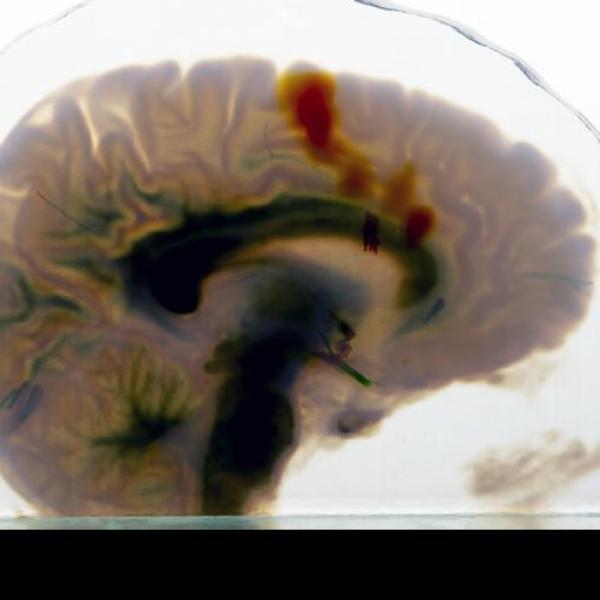

University of Colorado Boulder biochemistry professor Xuedong Liu was inducted into the National Academy of Inventors this year, recognizing a career of pioneering discoveries and real-world impact. His research on cellular communication has fueled four startups advancing novel treatments for cancer and neurodegenerative diseases.